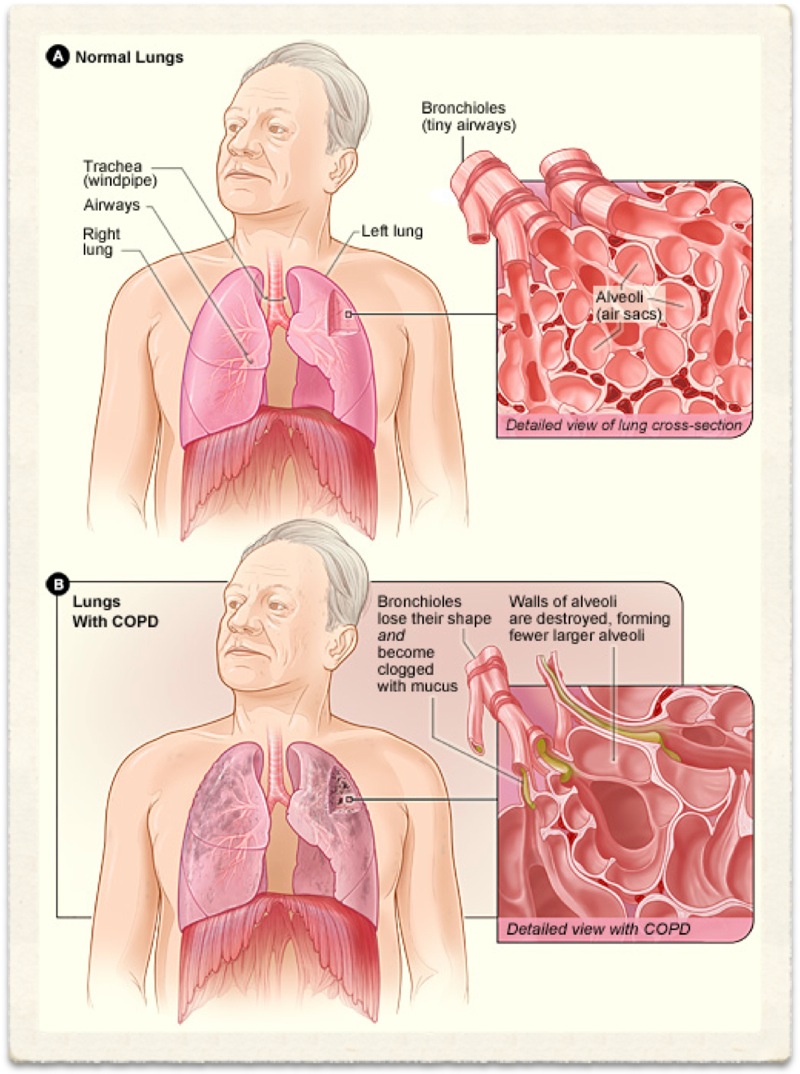

Chronic Obstructive Pulmonary Disease (COPD) is an 'umbrella' term for people with chronic bronchitis, emphysema, or both. With COPD the airflow to the lungs is restricted (obstructed). COPD is usually caused by smoking. Symptoms include cough and breathlessness.